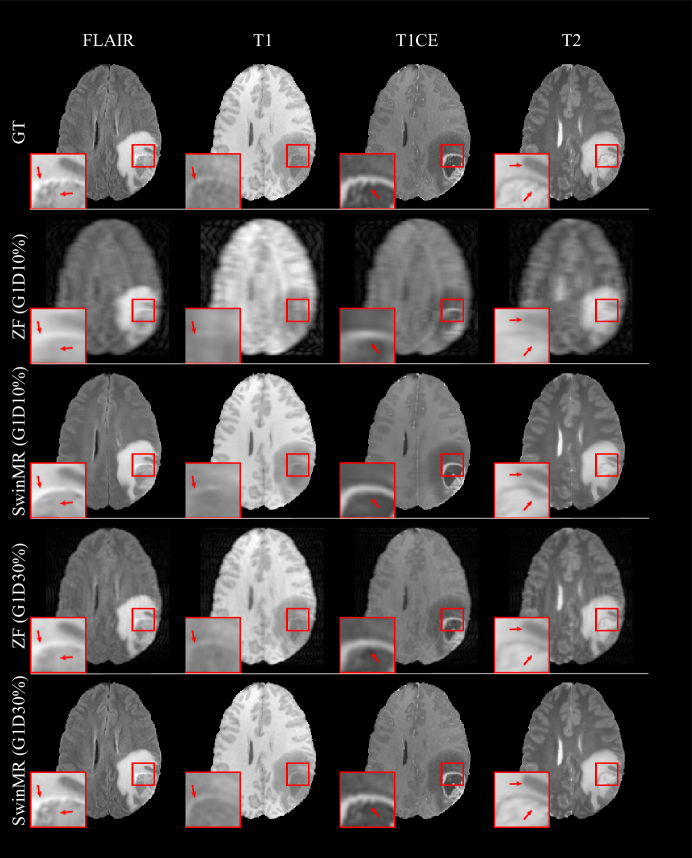

Table 4 shows the result of SwinMR trained with BraTS17 FLAIR, T1, T1CE and T2 respectively. Figure 18 displays the samples of the reconstruction of different modalities. Table 5 and Table 6 show the IoU and Dice score of the segmentation task. Figure 19 displays the sample of the segmentation task.

Refer to caption

Figure 18: Samples of reconstruction results for SwinMR on BraTS17 dataset including FLAIR, T1, T1CE and T2 MR images. Row 1: Ground truth MR images (GT); Row 2: Zero-filled MR images (ZF) undersampled by Gaussian 1D 10% mask (G1D10%); Row 3: Reconstructed MR images undersampled by G1D10%; Row 4: ZF undersampled by Gaussian 1D 30% mask (G1D30%); Row 5: Reconstructed MR images undersampled by G1D30%.